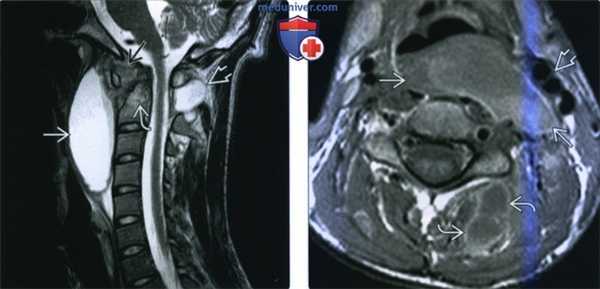

(Слева) На схеме сагиттального среза показан абсцесс шейного отдела спинного мозга, сопровождающийся отеком окружающей паренхимы спинного мозга и увеличением его объема на уровне абсцесса.

(Справа) Сагиттальный срез, Т2-ВИ: образование в центральной части спинного мозга с гиперинтенсивным содержимым и темным контуром, что характерно для воспалительных образований. Отек окружающей паренхимы спинного мозга распространяется краниально до продолговатого мозга и каудально до уровня грудного отдела. Подобная МР-картина не является специфичной для абсцессов, аналогично могут выглядеть первичные и вторичные новообразования спинного мозга. (Слева) Сагиттальный срез, Т2-ВИ, пациент со стрептококковым эндокардитом: диффузное увеличение объема спинного мозга с формированием в его толще на уровне С4-С5-6 кольцевидной зоны с низкоинтенсивной границей (капсула абсцесса).

(Справа) Сагиттальный срез, Т1-ВИ с КУ, пациент со стрептококковым эндокардитом: периферическое контрастное усиление сигнала капсулы абсцесса спинного мозга.